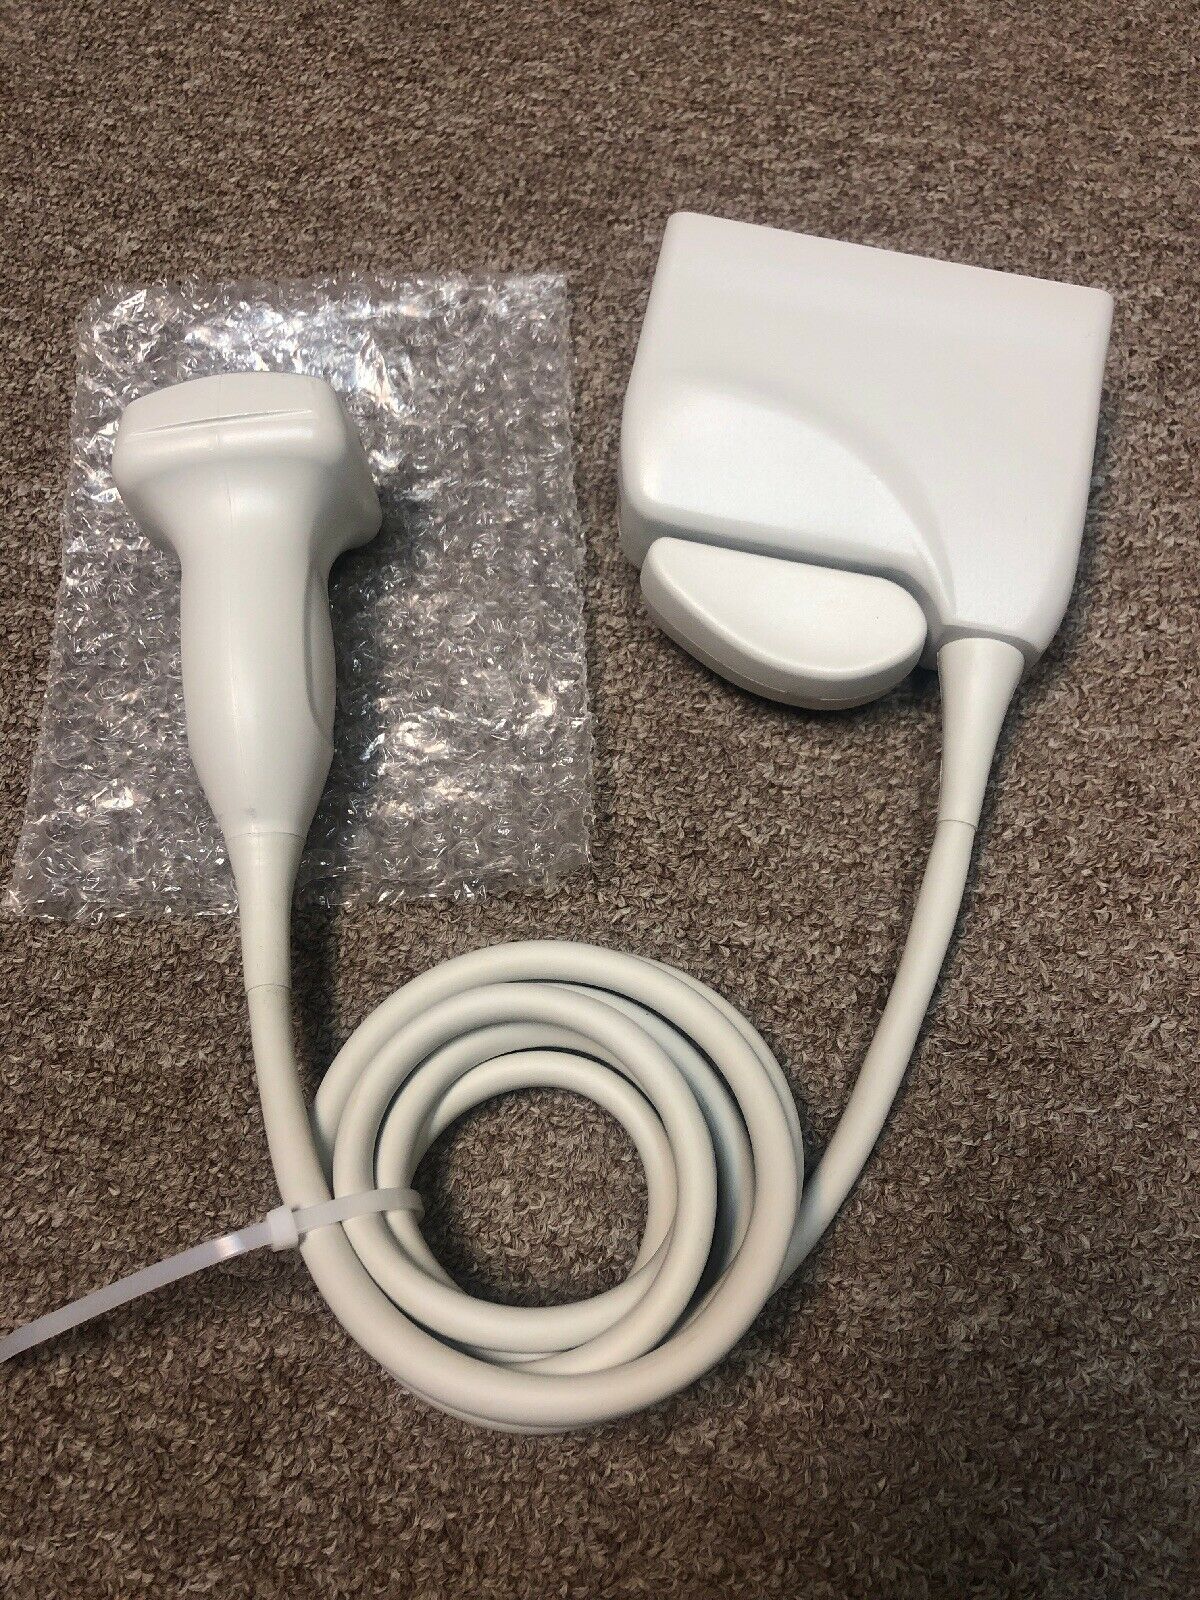

DIAGNOSTIC ULTRASOUND MACHINES FOR SALE

PHILIPS ULTRASOUND TRANSDUCER S4-1 PROBE

Sale price$ 1,228.36

DIAGNOSTIC ULTRASOUND MACHINES FOR SALE

PHILIPS S12-4 ULTRASOUND TRANSDUCER PROBE

Sale price$ 4,305.00